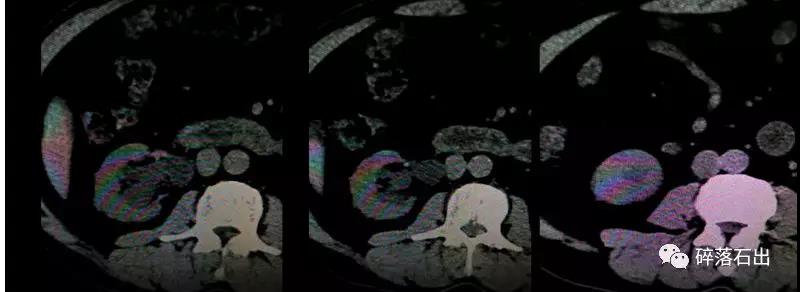

圖1圖2腎積水明顯,腎盂輸尿管中度擴(kuò)張;圖3輸尿管管壁不規(guī)則;圖4圖5圖6提示輸尿管結(jié)石切面輸尿管管壁厚度異常。

圖1 圖2 圖3